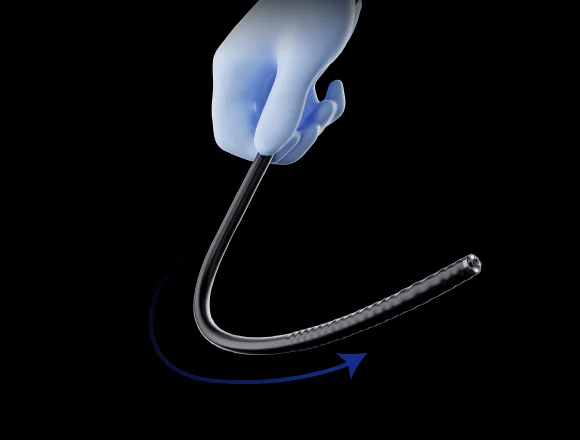

Эластичный изгиб

Во время эндоскопических процедур он может адаптироваться к различным изгибам толстой кишки. Способен саморегулироваться и поворачивать корпус эндоскопа к просвету в таких областях, как изгиб селезенки и печеночный изгиб, что уменьшает необходимость манипуляций с эндоскопом и повышает комфорт пациента.

Синхронизация передачи усилия

Инерционная конструкция во вводной части колоноскопа. Во время обследования он может передавать толкающие, вытягивающие и вращательные усилия, прилагаемые оператором к рукоятке, на дистальный конец колоноскопа, способствуя лучшему введению в цекум.